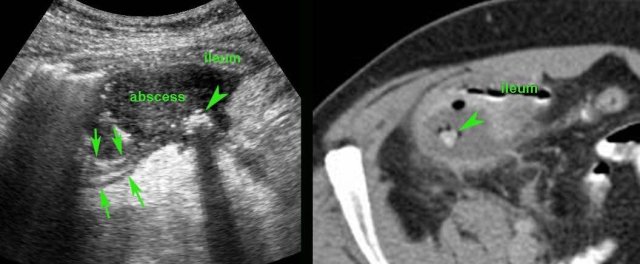

Patient with a small appendiceal abscess, ventrally walled-off by the ileum.

The appendix (arrows) is small because it has evacuated its purulent contents in to the abscess.

Note the calcified fecolith (arrowhead) on the bottom of the abscess.

Drainage was performed from laterally.

This 75-year old lady had subsiding symptoms after 7 days of RLQ pain, and she told us that she was feeling much better now.

US showed an inflamed appendix (arrow) with an adjacent abscess, walled-off by inflamed fat and the terminal ileum.

There were echolucent connections (*) between the abscess and the ileum, indicating spontaneous evacuation (a and v = right iliac artery and vein).

CT scan confirmed the anatomic situation.

The patient was completely cured with only antibiotics.

Three years later she underwent CT for sigmoid diverticulitis which allowed us to take a look at her appendix region.

The appendix (arrows) was small and still had intimate contact with the ileum (il.)

Another 4 years later, at age 82, she is still doing fine.